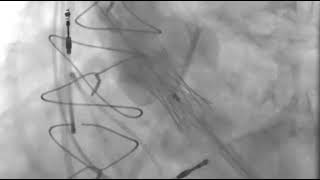

Video 6

Transapical transcatheter aortic valve replacement.